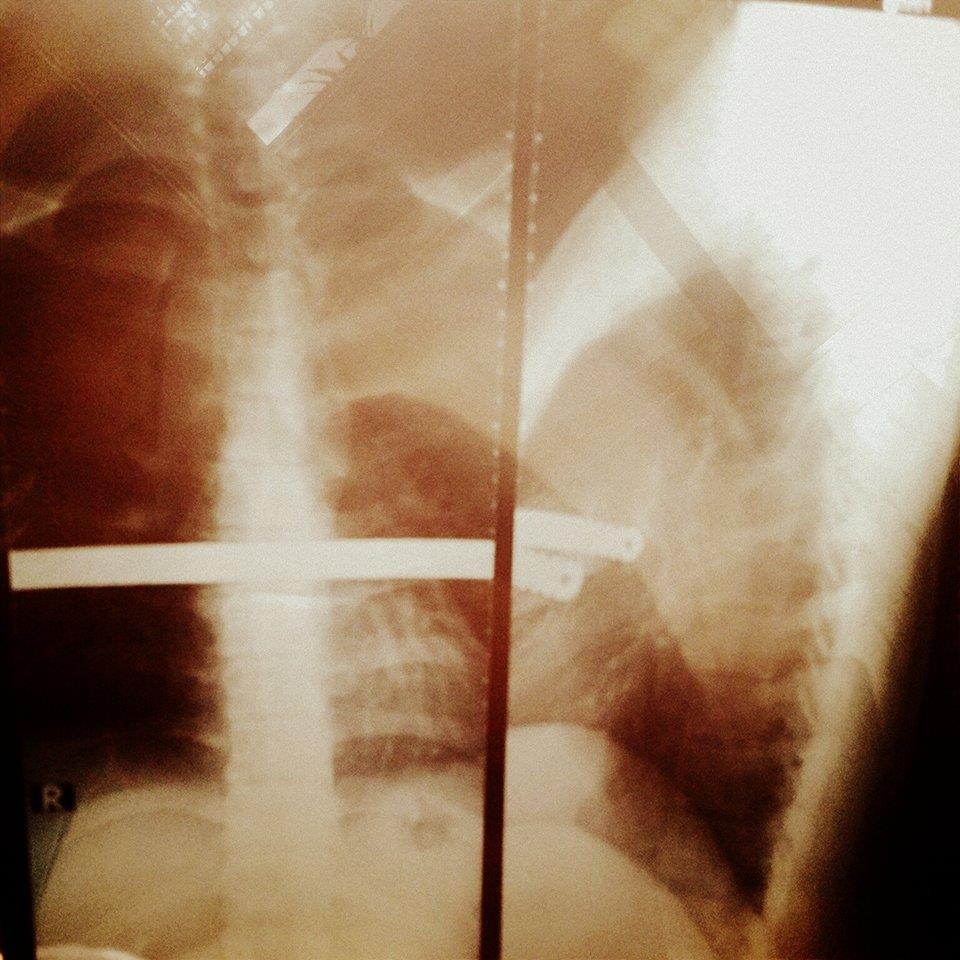

| Thanh sắt dài 30,5 cm trong lồng ngực Khánh suốt 3 năm qua. |

Dù rất đau lòng nhưng để giữ mạng sống cho con trai, gia đình anh chấp nhận phẫu thuật, chèn thanh sắt dài 30,5 cm trong lồng ngực Khánh. Suốt 3 năm qua, dù chung sống với "vật thể lạ" trong người nhưng 9X luôn động viên mình vượt qua.

Duy Khánh cho biết thanh sắt này chèn vào lồng ngực có tác dụng định vị xương tim và duy trì sự sống cho trái tim bệnh nhân. Hạn sử dụng tối đa của thanh kim loại này là hai năm, nhưng vì mải mê tham gia các hoạt động nghệ thuật nên Khánh đã trễ hẹn với bác sĩ một năm. Thời gian gần đây, những cơn đau lại xuất hiện.